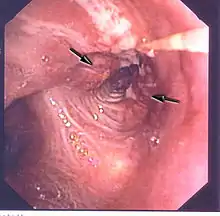

Obstruction d'une bronche par une tumeur

Obstruction d'une bronche majeure par un cancer du poumon : vue bronchoscopique.

La radiographie thoracique est la première mesure à prendre si un patient se plaint de symptômes pouvant suggérer un cancer du poumon. Ceci peut révéler une masse évidente, un élargissement du médiastin (qui suggère une extension aux ganglions lymphatiques qui s'y trouvent), une atélectasie (affaissement), une inflammation (pneumonie) ou un épanchement pleural. En l'absence de signes radiographiques, mais si les soupçons sont élevés (par exemple, un gros fumeur avec hémoptysie), une bronchoscopie ou un scanner peuvent donner l'information nécessaire. La bronchoscopie ou la biopsie guidée par scanner sont souvent utilisées pour identifier le type de tumeur[3].